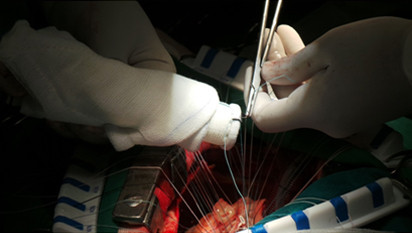

Surgery of Replacing The Ascending Aorta using Artificial Valved Conduit

Artificial Graft And anastomosing the Coronary Buttons